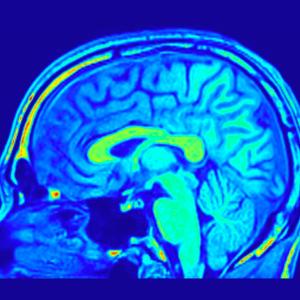

Литият може да намали риска от развиването на деменция